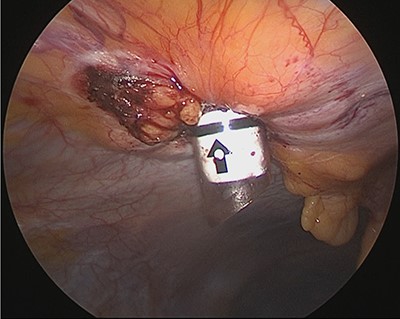

We inserted the system’s 12-mm trocar into the hernia orifice (Fig. 6) and inserted the guide through the trocar. A suture was inserted into the abdominal cavity from the 1:30 position using a passer, and the passer was reinserted at the 7:30 position to pull out the suture. The trocar was then rotated 90° counterclockwise. The suture that now emerged from the 10:30 position was grasped with a passer and returned once more to the abdominal cavity, where it was grasped with the passer now inserted from the 4:30 position and pulled back to the outside of the wound (Fig. 7). The trocar was removed, and after confirming that the Z suture was completed, the thread was ligated (Fig. 8). The operative time was 1 h and 20 min, and the amount of bleeding was 5 ml.